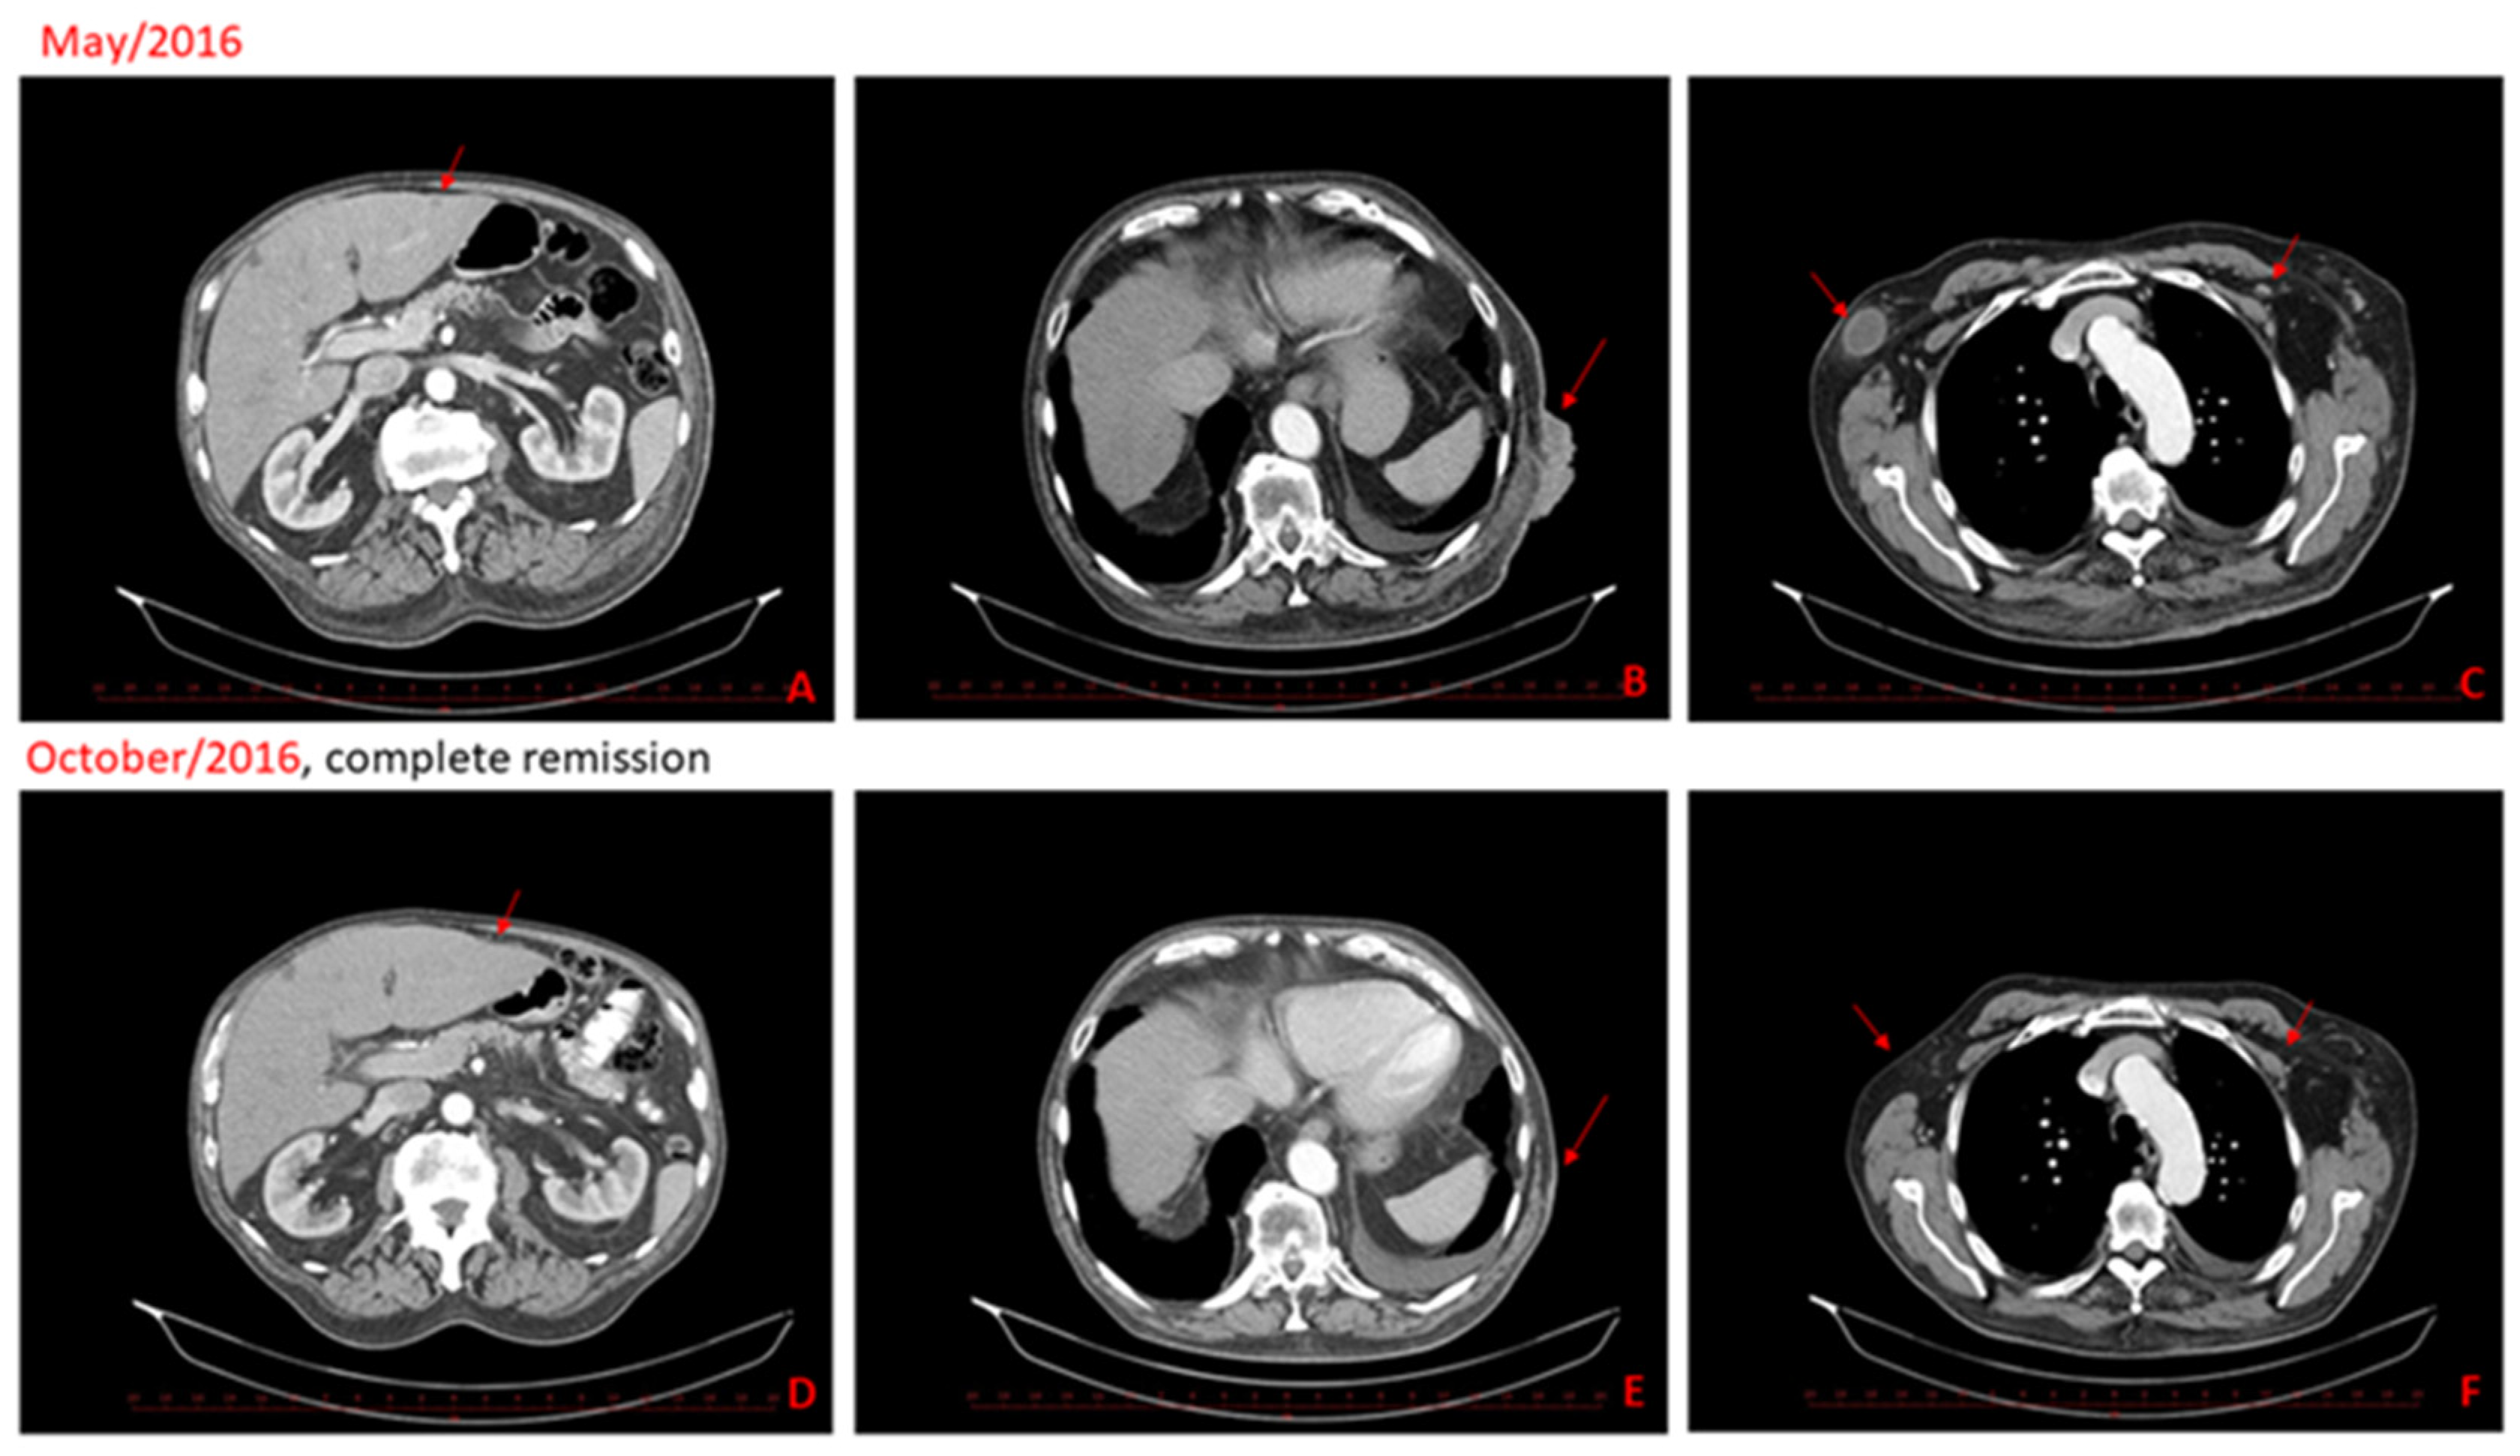

Figure 2.

CT scans from May 2016 show progressive disease, new liver metastasis (A), skin and subcutaneous metastasis (B), left subclavicular node metastasis and right node axillary metastasis (C). CT scans in the second-line show complete remission of the metastatic disease, two months after cryotherapy and half a year after the last dose of ipilimumab (D–F).

Contrary to the situation before the cryotherapy, the cutaneous, liver and axillary lymph node metastases were not detected on the control CT scan (Figure 2D,F) two months after cryotherapy (approximately fourth months after the last ipilimumab administration). An excellent clinical response was apparent as early as two months after cryotherapy, where almost healed sites of cutaneous metastases were observed (Figure 3A–F). Excellent clinical response and fully healed skin lesions were documented during a regular follow-up visit six months after cryotherapy (Figure 3F). The complete response was maintained for 13 months after cryotherapy and 15 months after the last application of ipilimumab. The patient ceased suddenly due to myocardial infarction 15 months after cryotherapy, aged 79, without any clinical signs of melanoma recurrence. The autopsy also did not show any recurrence of melanoma.